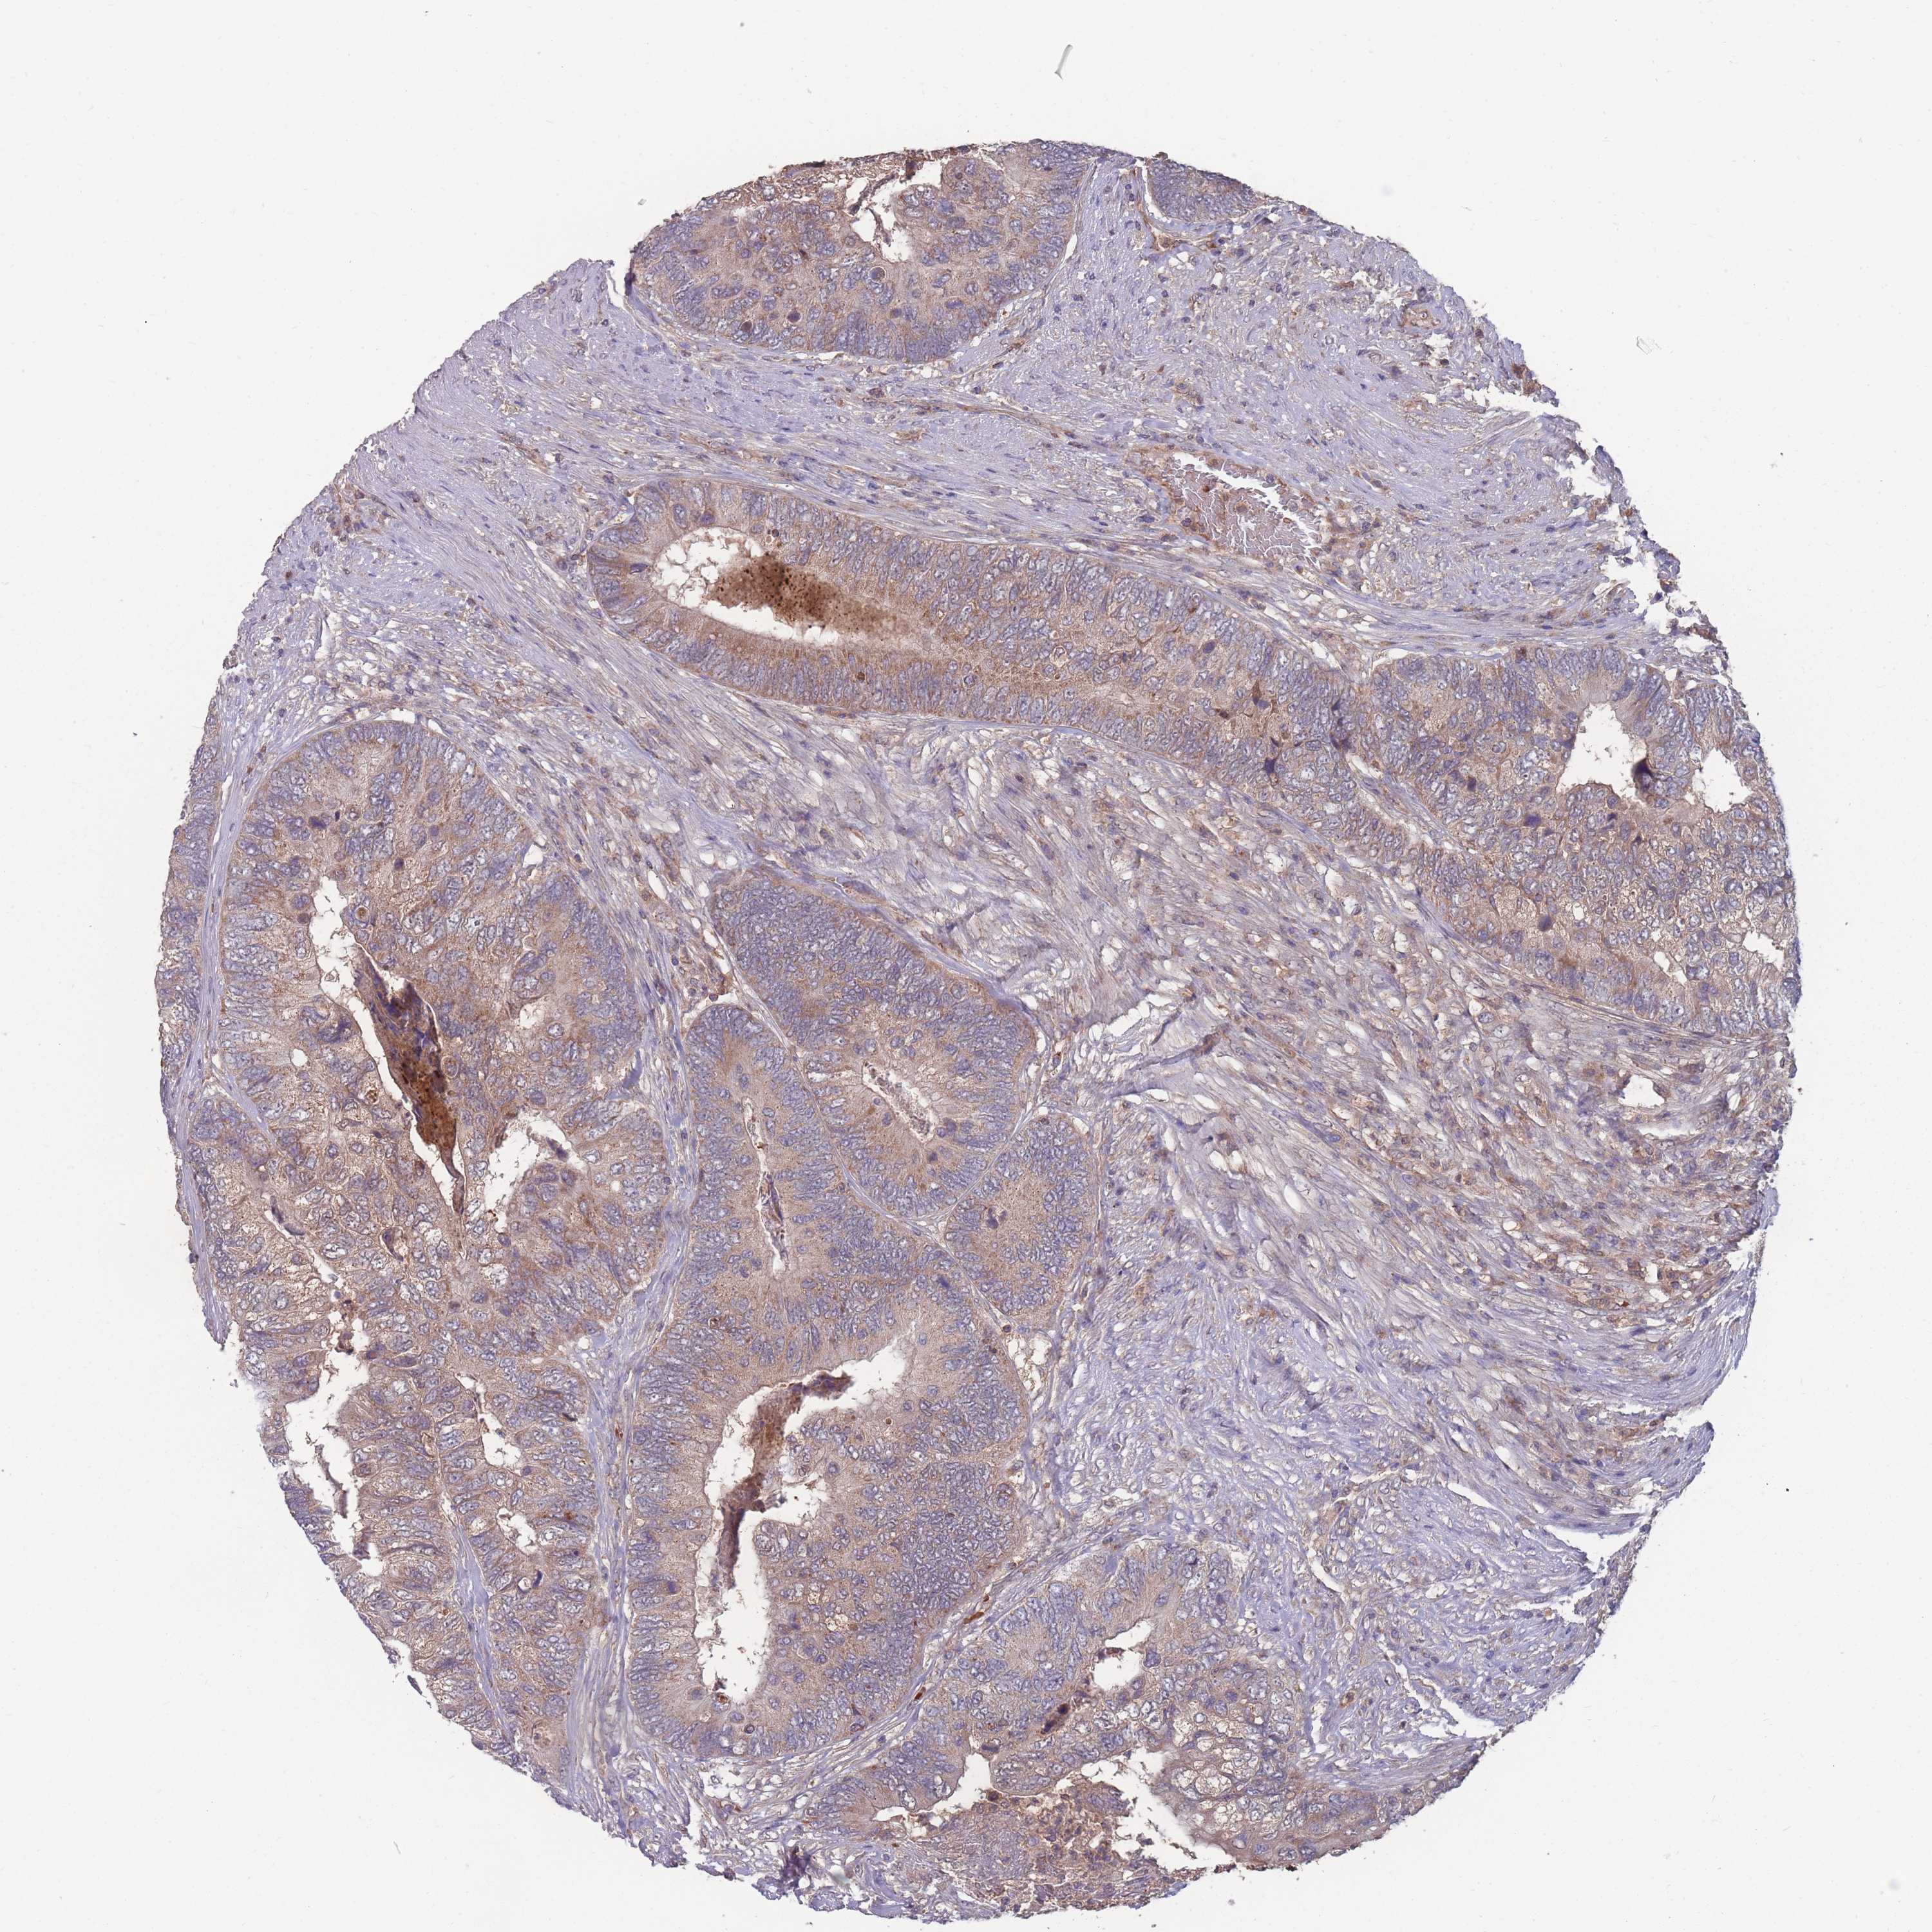

CANCER COLORECTAL CANCER Show tissue menu

ANTIBODIES

AND

VALIDATION